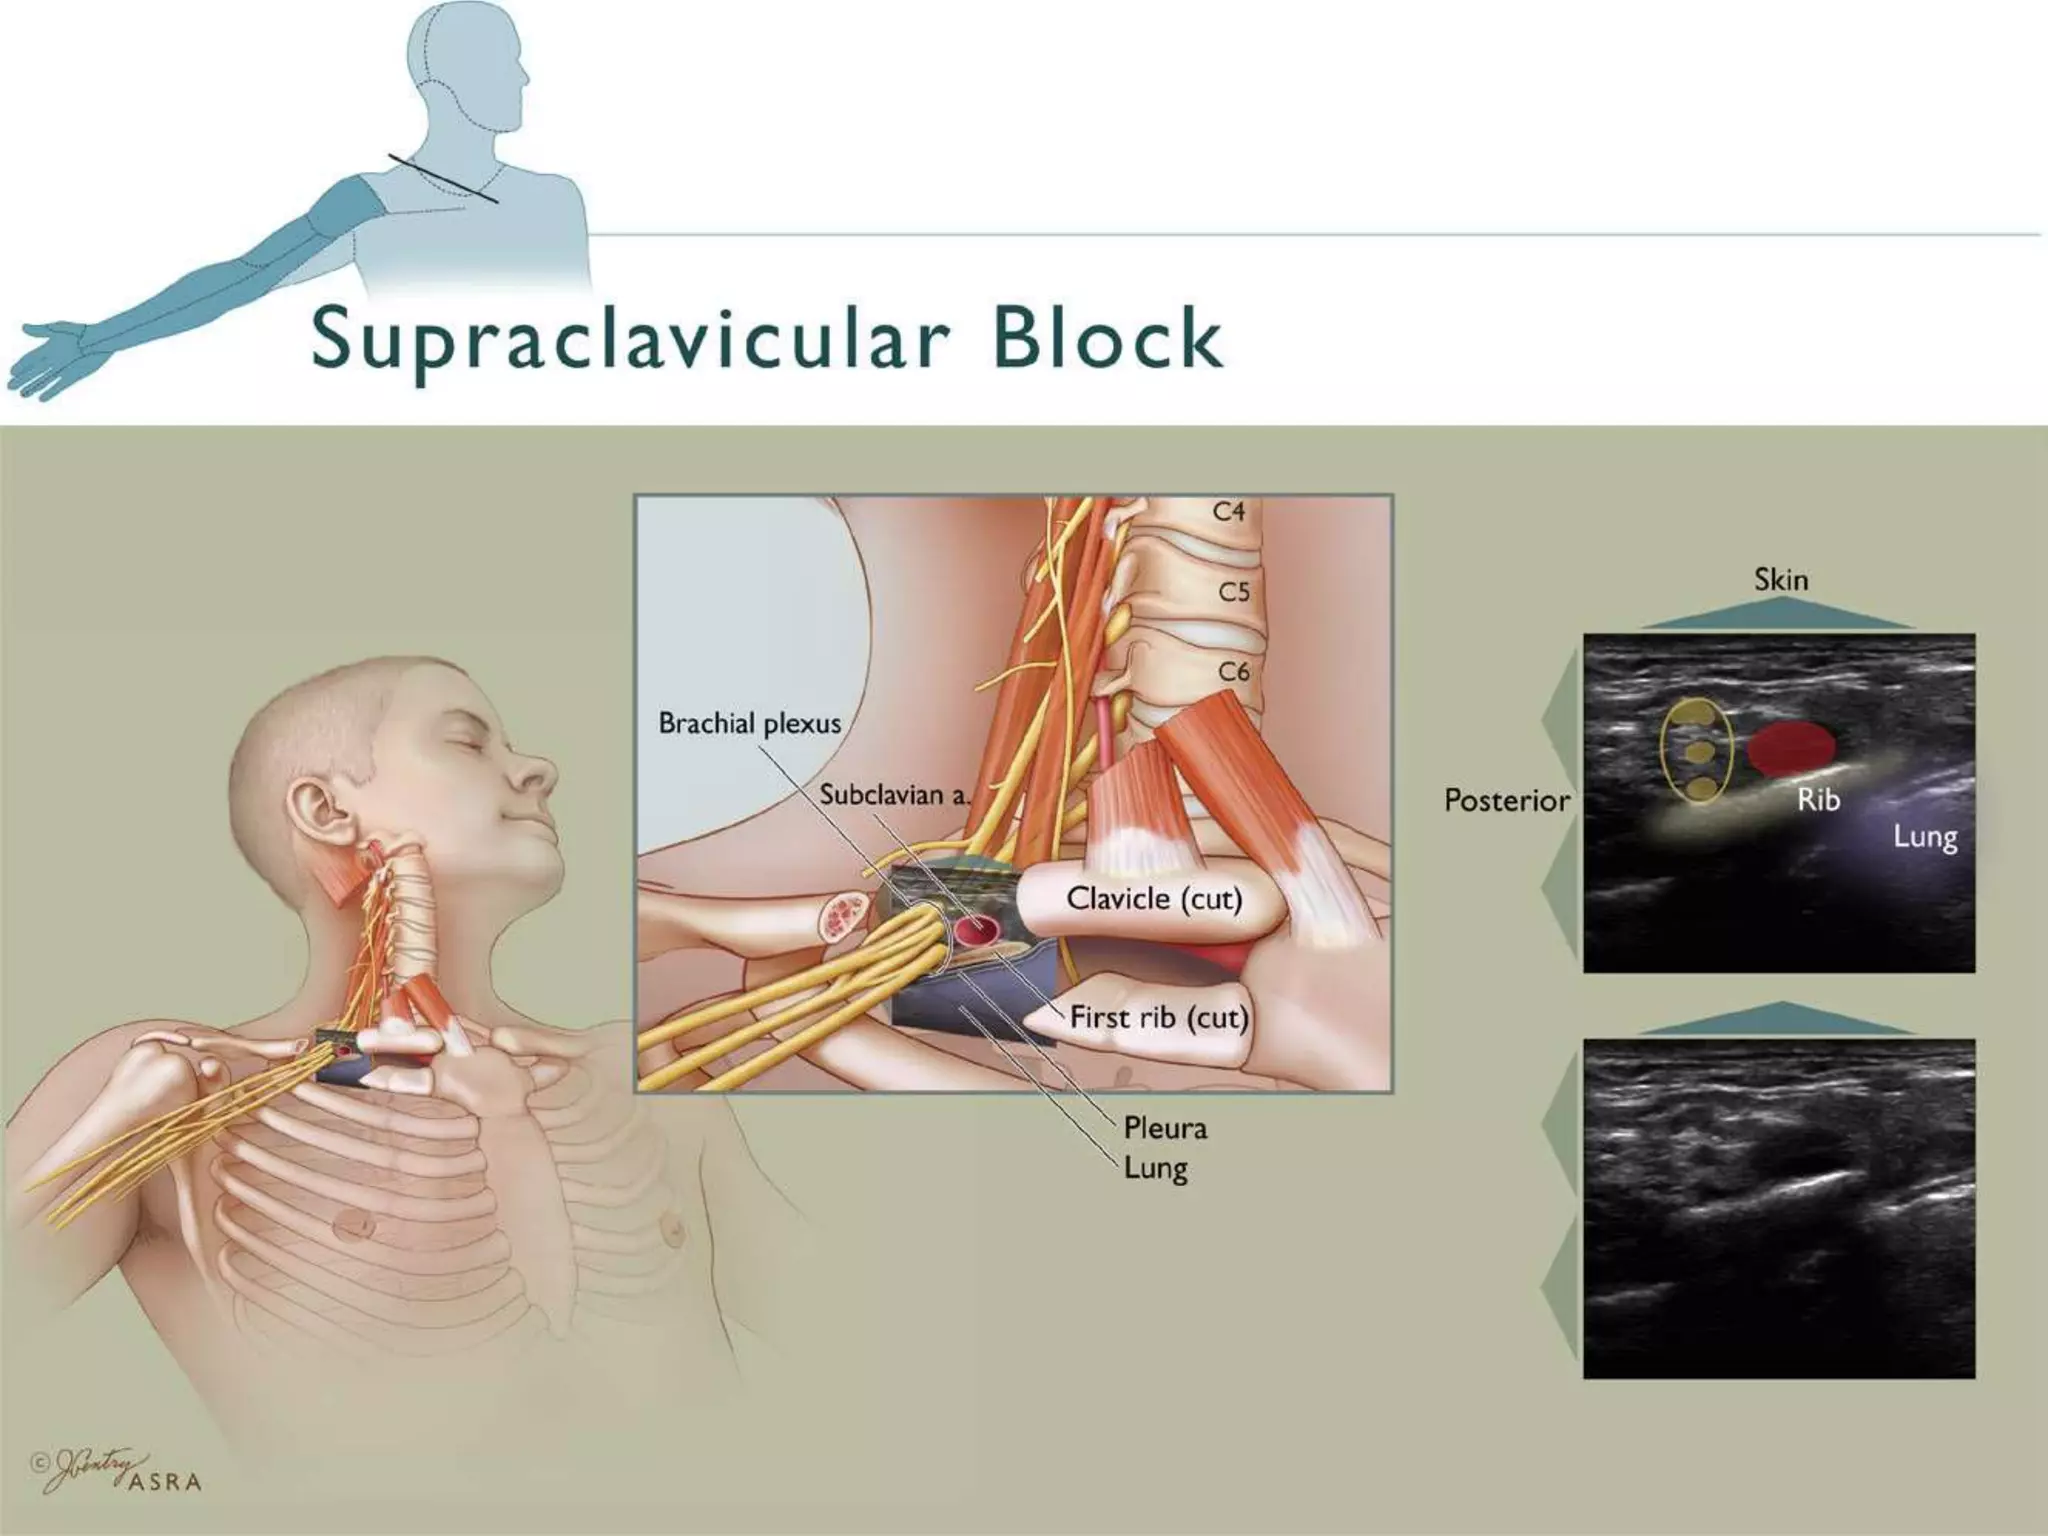

This document provides an overview of brachial plexus anatomy and techniques for brachial plexus nerve blocks. It begins with a description of the brachial plexus formation from cervical and thoracic nerve roots and its branching pattern. Four main approaches for brachial plexus nerve blocks are described: interscalene, supraclavicular, infraclavicular, and axillary. Details are provided on the anatomy and techniques for performing interscalene and supraclavicular brachial plexus blocks. Ultrasound guidance is discussed as an advancement which allows real-time visualization of needle and nerve. Complications are also summarized.